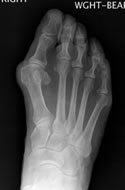

I'm 64 years old and have just recovered from surgery to correct a bunion and hammertoe. I've been wearing sneakers for the past 2-3 years because regular shoes were just too painful, and I work on my feet at a full-time job. I went to a doctor in Salem and he told me I would need surgery, and he referred me to Dr. Ken Leavitt. Being the skeptic that I am, I decided to get another opinion from a doctor closer to my home in Danvers. He suggested a surgery that would have me back on my feet in two weeks (vs. eight), but I had already been advised not to go that route unless I wanted to go back in a year and have it done again.

I hadn't had surgery since I was 6 years old for a tonsillectomy, so, needless to say, I was terrified! Once I met Dr. Leavitt, I was reassured and decided to go ahead with the surgery. He told me it would be a 4-month recovery and two months would be non-weight bearing. My husband had just died and I would be alone, so I began planning ahead. I arranged my home to be on the first floor during my recovery. I started physical therapy and did my exercises faithfully to build up my strength to use crutches. I purchased a "Roll-a-bout" and later a "Knee Walker" - both of which were extremely helpful.

My new foot looks great. My physical therapist said she thought it looked beautiful and that was not always the case. I can barely see where the incision was. The eight weeks that I was non-weight bearing was a small price to pay in the scheme of life to have a good foot under me afterward. I was forewarned to follow instructions and "Take Care of My Work" and it paid off. I'm glad I had the surgery and I would do it all again. If you are in need of a foot doctor, look no further; call Dr. Ken Leavitt.